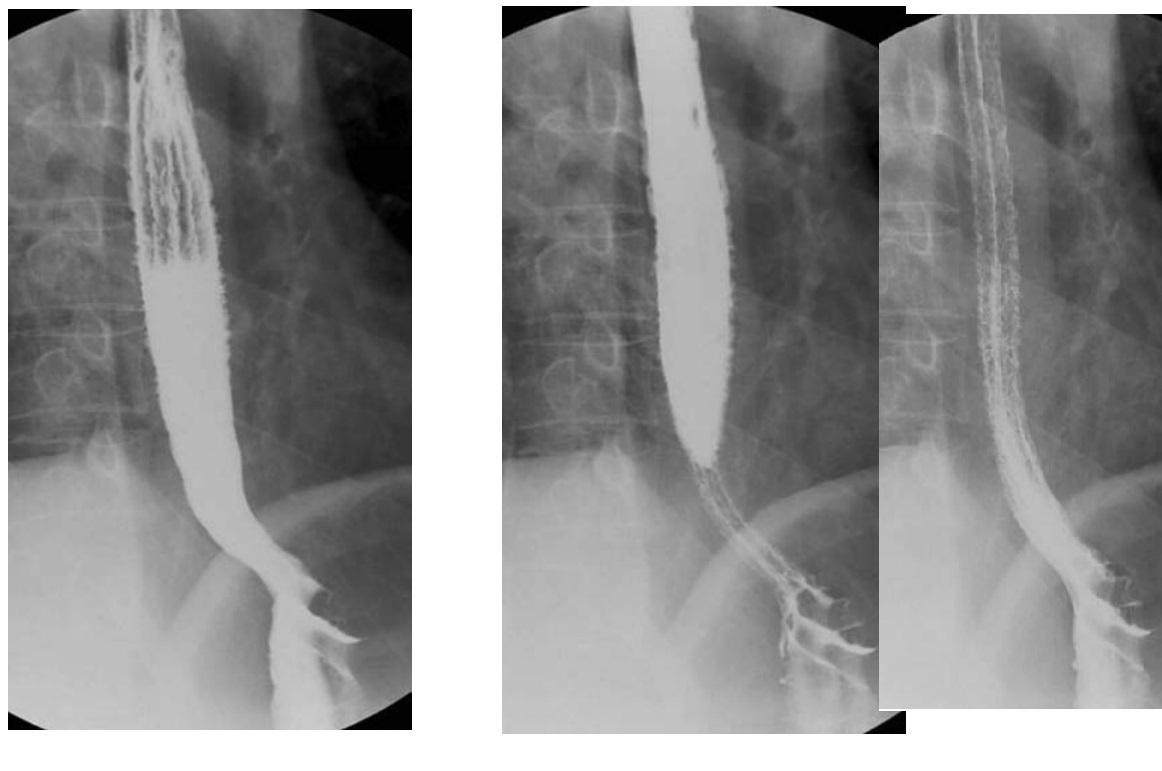

Caustic

long stricture ± diffuse ulceration of lower and mid oesophagus

Stomach can be pulled into the chest as the oesophagus shortens and strictures

DDX Long stricture

-NG tube in too long or radiation - These are usually smooth